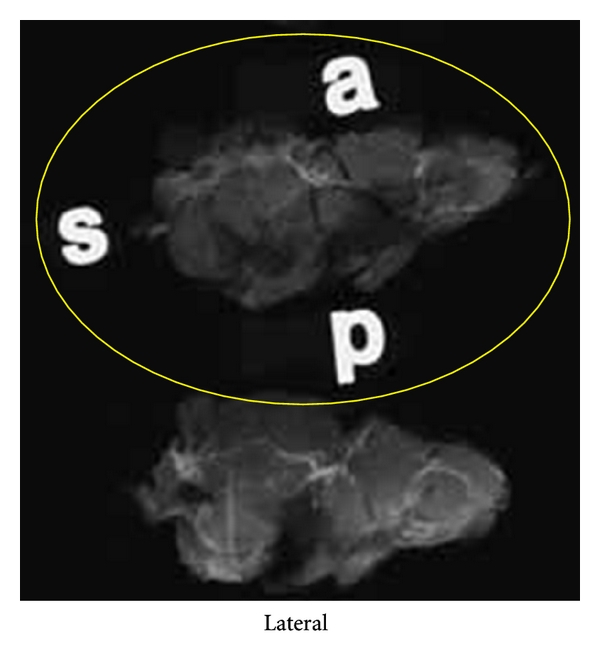

Upon receipt in the surgical pathology suite, all specimens are checked for proper surgical orientation, and any deficiencies identified are promptly corrected by the surgeon. All surgical margins are marked before sectioning with India ink with a discrete color coded to each of six axial margins. Mastectomy specimens are sectioned in the sagittal plane at uniform 5 mm increments with preservation of medial-to-lateral sequence and cephalocaudad orientation. Initially, 100% of each mastectomy specimen was submitted for specimen radiography. Experience permitted introduction of time and cost conserving measures so that approximately one-half to two-thirds of each specimen was submitted for radiography, focusing on the location of previous biopsy or lumpectomy sites and any additional guidance provided by breast surgeons and imagers. Breast-conserving specimens and reexcisions are inked for margins and sectioned at 5 mm increments. The plane of sectioning varies with the requirements of the case. Occasionally, demonstration of maximum extent of disease or multifocality in one plane is of paramount importance. In these cases, the plane of sectioning is guided by image interpretation of size, extent, and multifocality, and sections are typically made in the coronal (frontal) plane. In cases where the status of chest wall or anterior cutaneous margins (or both) are of particular concern or the sagittal plane shows maximum extent, the sagittal plane is selected for sectioning and large-format section submission. This approach allows convenient correlation of sagittal large histology sections with MRI sagittal-reconstructed images. All BCS and reexcision specimens are entirely submitted for specimen radiography.

Orientation of all specimens is maintained with the use of radioopaque alphabet characters to denote axis margins in each plane as well as the sequence of sections, for example, “superficial to deep” in the coronal plane or “medial to lateral” in the sagittal plane. Tissue slices are placed on previously exposed radiographic film with orienting characters and transported expeditiously to the breast imaging facility for radiography. Following specimen radiography and radiographic interpretation (vide infra), the specimen with accompanying radiographs is returned for pathologic examination with a “Large-Format Specimen Checklist” detailing the clinical and specimen radiographic findings in written narrative and using template diagrams of both breasts. This worksheet communicates the clinical and radiographic findings of concern with specific questions to be addressed pathologically. Imaging abnormalities visible mammographically are marked directly on the films with a wax pencil as a guide for histopathologic section submission (Figure 1). The location and extent of ultrasound or MRI-detected findings, not visible mammographically or with specimen radiography, are marked on the specimen radiographs. Section(s) best demonstrating critical findings such as proximity to margins or maximum extent of neoplasm are encircled for possible large-format submission.

Following traditional pathologic specimen examination with gross inspection and palpation, sections are selected for histologic study to incorporate gross pathologic findings as well as findings of concern communicated by imagers and surgeons (Figure 2). Microscopic evaluation of surgical margins is typically accomplished with a combination of both large-format and conventionally sized tissue blocks. Large sections usually permit margin evaluation along 100% of the circumference of a BCS specimen and are selected to encompass critical margins whenever close proximity to a surgical line of excision is suspected. Margins perpendicular to the large-format plane of section are usually submitted as conventional tissue blocks. Orientation of all conventionally sized margin sections is perpendicular to the specimen surface to allow measurement of margin width to the nearest whole millimeter. The precise location of these perpendicular margins is selected with guidance from both imaging and clinical information and conventional pathologic examination. Reexcision specimens, including surgical shave excisions of biopsy cavities, are sectioned and oriented perpendicular to the surgical margin so that margin distance from the cavity to the new surgical margins remains measureable. The anatomic location of all tissue blocks removed from the specimen is recorded in the gross dictation narrative of the pathology report as well as on the specimen radiographs which are preserved as a permanent record of pathology slide origin. This record is provided to the pathologist at microscopic sign-out as an aid in the reconstruction of the specimen in three dimensions.

2.4. Breast Imaging Department Specimen Radiography Protocol

Upon receipt in the imaging center, specimens are placed in an analog specimen radiography unit (Faxitron Bioptics, LLC). Specimen film images are examined by a breast imager, and all relevant mammograms, core biopsy specimen radiographs, wire-localization images, ultrasound, and MRI studies are reviewed. Mammographically detected lesions of concern are marked on the radiograph films, and the location of mammogram occult abnormalities identified with ultrasonography and MRI is encircled. To facilitate communication of clinical, presurgical imaging and specimen radiography findings to the pathologist, the “Large-format Specimen Checklist” is completed with reference to notations made by the imager on the specimen radiographs. A graphical depiction of the location and extent of clinical and imaging-suspected neoplasia is marked on a template bilateral breast diagram. A written narrative conveys clinical concerns and imager-initiated questions for pathologist reconciliation. This form is returned with the specimen and annotated specimen radiographs to the surgical pathology suite.